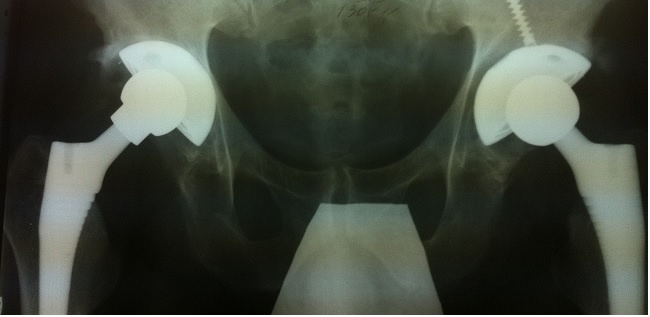

Двухстороннее протезирование тазобедренных суставов разными моделями протезов